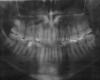

Leonid_ Опубликовано 8 ноября, 2010 Поделиться Опубликовано 8 ноября, 2010 Здравствуйте! Недавно пролежал 2 недели в больнице с диагнозом хронический гайморит. С помощью пункций правую пазуху до конца очистить не удалось. Выделения имели специфический запах. Врач рекомендовала сделать панорамный снимок и проконсультироваться у стоматолога. Кстати, за две недели до больницы у дантиста я был. Внешне все оказалось в порядке. Болевых ощущений тоже никаких. Вот снимок. Ссылка на комментарий

Aldo Rain Опубликовано 9 ноября, 2010 Поделиться Опубликовано 9 ноября, 2010 снимок конечно не качественный но по нему ничего плохого с зубами неть Ссылка на комментарий

Снежана Опубликовано 9 ноября, 2010 Поделиться Опубликовано 9 ноября, 2010 у вас снимок в печатном виде? если да, то лучше сходить в клинику, взять в цифровом варианте, если на пленке, то попробовать оцифровать еще раз с улучшением качества изображения, на том, что вы показали ничего не видно. и обозначьте на снимке где лево, где право. а именно интересует с какой стороны на верхней челюсти во рту нет восьмого зуба.у вас был односторонний гайморит или двухсторонний? Ссылка на комментарий

Лялька Опубликовано 9 ноября, 2010 Поделиться Опубликовано 9 ноября, 2010 у вас снимок в печатном виде? если да, то лучше сходить в клинику, взять в цифровом варианте, если на пленке, то попробовать оцифровать еще раз с улучшением качества изображения, на том, что вы показали ничего не видно. и обозначьте на снимке где лево, где право. а именно интересует с какой стороны на верхней челюсти во рту нет восьмого зуба.у вас был односторонний гайморит или двухсторонний? Нечто белеется над верхним зубом мудрости(предполагаю правым) Может сверхкомплектный? Эх,качество изображения страдает Хотя,далековато он от пазухи... Ссылка на комментарий

Снежана Опубликовано 10 ноября, 2010 Поделиться Опубликовано 10 ноября, 2010 формально это как? вам на основании чего поставили диагноз? если на рентгене были изменения в пазухах с обоих сторон, то это не формальный, а нормальный двухсторонний гайморит, он чаще бывает не от зубов, а как осложнение различных ОРВИ, но при этом процесс в одной пазухе может быть выражен сильнее, возможно это ваш случай. Но все таки именно справа у вас есть образование, как здесь правильно отметили, очень напоминающее сверхкомплектный зуб, в области восьмерки, довольно близко прилежащее к дну верхнечелюстной пазухи. По ОПГ сверхкомплектный и пазуха четко отграничены друг от друга достаточным количеством кости. Но, еще раз но) для того чтобы полностью исключить одонтогенную природу гайморита, я своему пациенту назначила бы КТ, прежде чем рекомендовать делать операцию по прочистке пазухи. Иногда там бывают сюрпризы. На данный момент у вас имхо статус недообследован. Ссылка на комментарий